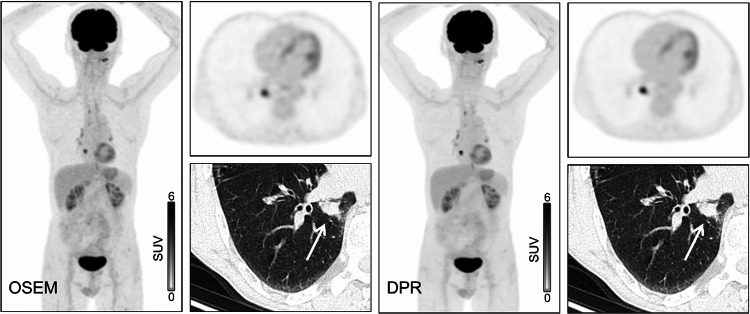

Objectives: The present study aimed to investigate the influence of the deep progressive learning reconstruction (DPR) algorithm on the 18F-FDG PET image quality and quantitative parameters.

Methods: In this retrospective study, data were collected from 55 healthy individuals and 184 patients with primary malignant pulmonary tumors who underwent 18F-FDG PET/CT examinations. PET data were reconstructed using the ordered subset expectation maximization (OSEM) and DPR algorithms. The influence of DPR algorithm on quantitative parameters was explored, including the SUVmax, SUVmean, standard deviation of SUV (SUVSD), metabolic tumor volume (MTV), total lesion glycolysis (TLG), and tumor-to-background uptake ratio (TBR). Finally, the differences in image quality parameters, including signal-to-noise ratio (SNR) and contrast-to-noise ratio (CNR), between the two reconstruction algorithms were evaluated.

Results: DPR algorithm significantly reduced the SUVmax and SUVSD of background tissues (all, P < 0.001) compared to OSEM algorithm, while no statistical difference was observed in SUVmean between the two algorithms (all, P > 0.05). DPR algorithm notably increased the SUVmax, SUVmean, and TBR of lesions (all, P < 0.001) and reduced MTV (P = 0.005), with minimal differences in TLG noted between the reconstruction algorithms (P < 0.001). The percentage differences in SUVmax (P = 0.001), SUVmean (P = 0.005), and TBR (P = 0.001) between the two algorithms were significantly higher in solid nodules than in pure ground glass nodules (pGGNs). The ΔCNR between solid nodules (P = 0.031) and mixed ground glass nodules (P = 0.020) was greater than that between pGGNs. SNR and CNR obtained using the DPR algorithm were markedly improved compared to those determined using the OSEM algorithm (all, P < 0.001).

Conclusion: Under identical acquisition conditions, the DPR algorithm enhanced the accuracy of quantitative parameters in pulmonary lesions and potentially improved lesion detectability. The DPR algorithm increased image SNR and CNR compared to those obtained using the OSEM algorithm, significantly optimizing overall image quality. This advancement facilitated precise clinical diagnosis, underpinning its potential to significantly contribute to the field of medical imaging.